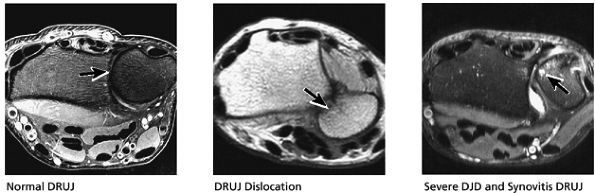

FIGURE 10.32 ● Normal axial anatomy. (A) Fractures of the hook of the hamate, commonly occult on plain films, are easily visualized on axial MR images through the hamate. (B) The flexor carpi radialis is visualized cradled by the hook of the trapezium. This is a common location for tenosynovitis and tendinosis of the flexor carpi radialis tendon. (C) The thenar muscles (abductor and flexor pollicis brevis) are visualized volar to the radial aspect of the distal carpus. Median neuritis should be suspected when selective fatty atrophy or denervation of the thenar muscles is visualized. (D) The median nerve within the carpal tunnel may display evidence of median neuritis, such as increased signal or enlargement. A mass lesion of the carpal tunnel at this level may cause mass effect within the carpal tunnel and impinge the median nerve. (E) The pisotriquetral joint is a common location for severe degenerative arthritis and synovitis, associated with significant ulnar-sided pain. (F) The extensor pollicis longus crosses obliquely dorsal to the extensor pollicis longus and brevis tendons. This is a not uncommon location for tears of the extensor pollicis longus tendon. (G) The scapholunate articulation is a common location for ganglion cysts, usually found directly dorsal to the scapholunate ligament. Even small dorsal ganglion cysts in this location can be exquisitely tender and painful. Often, a small neck of fluid signal extends from the dorsal ganglion cyst back toward the scapholunate ligament, and in certain cases a small perforation of the scapholunate ligament can be suggested. (H) The extensor pollicis brevis and abductor pollicis longus tendons are located lateral to the distal radius. Tendinosis and tenosynovitis of these tendons is known as de Quervain's stenosing tenosynovitis. (I) Not uncommonly the extensor carpi ulnaris tendon is subluxed over the ulnar styloid, particularly when the patient is supinated, with the ulnar styloid pointing dorsally. This is not necessarily an abnormal finding, particularly when the extensor carpi ulnaris tendon otherwise appears normal. (J) The triangular shape of the TFC complex is best appreciated on axial images, with the apex of the triangle attaching at the ulnar styloid and the broader base of the triangle attaching at the radius. (K) The distal radioulnar joint is examined in the axial plane to view the alignment of the radius with respect to the ulna. The ulna lies within the concave groove in the medial aspect of the radius called the sigmoid notch, and the two bones lie grossly in the same plane. Mild apparent dorsal shift of the ulna with respect to the radius is normal when the wrist is scanned in full pronation (the ulnar styloid pointing ulnar-volar). (L) When the triangular fibrocartilage is torn, or if there is a displaced fracture at the base of the ulnar styloid, the distal radial ulnar joint may become somewhat destabilized, ultimately resulting in degenerative arthrosis and synovitis. Another cause of distal radioulnar joint degenerative change is the ulnar impingement syndrome, in which a short ulna erodes the ulnar aspect of the distal radius.

The dorsal radioulnar ligament and palmar radioulnar ligament are the primary ligamentous stabilizers of the distal radioulnar joint and on axial plane images are seen coursing on both the dorsal and volar sides of the TFC, at the level of the base of the ulnar styloid, where the ligaments insert. Tears of the dorsal radioulnar ligament are associated with volar subluxation of the ulna. Tears of the volar radioulnar ligament are associated with dorsal subluxation of the ulna. Distal radioulnar joint instability is suggested when the ulnar head is abnormally subluxed or dislocated with respect to the radius, beyond the normal range of motion allowed for pronation and supination. In addition to ligamentous injury, osseous injuries such as fractures at the base of the ulnar styloid also may lead to distal radioulnar joint instability.